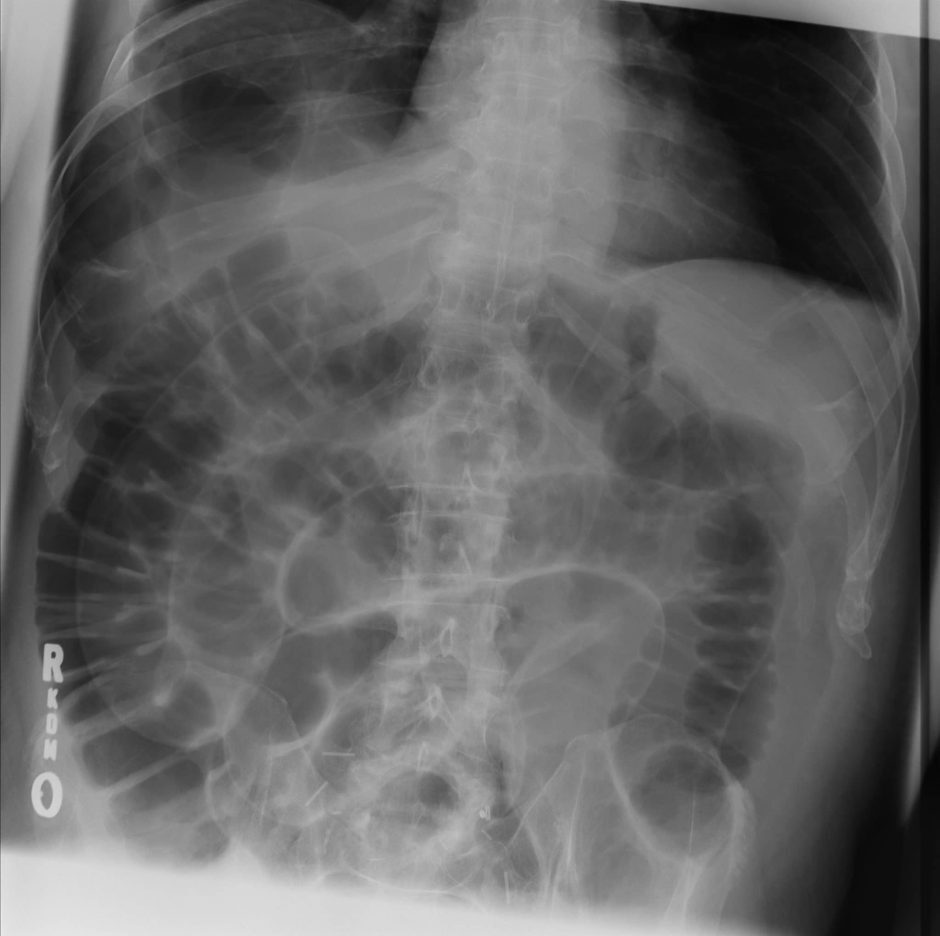

Q

what does this AXR show?

A

large bowel obstruction

- peripheral bowel loops

- large dilated bowel loops >6cm diameter

- haustra partially crosses diameter of bowel